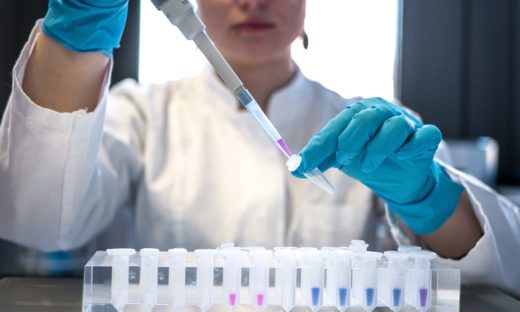

現在の証拠は、アセトアミノフェンが完全に安全であるという仮定に重大な疑問を投げかけています。2022年の系統的レビュー²⁴では、乳幼児におけるアセトアミノフェン使用が神経発達に対して安全性が証明されたことは一度もないことが明らかになりました。

医学界の反応やNBCの報道は、まるで法廷で検察側の証拠だけを提示して判決を下すようなものでした。これは、オメガ3(プーファ)、エストロゲンやセロトニンなどの礼賛や砂糖悪玉説にも言えることです。真のサイエンスは、都合の良い証拠だけを選び出すのではなく、すべての証拠を公平に評価することから始まります。